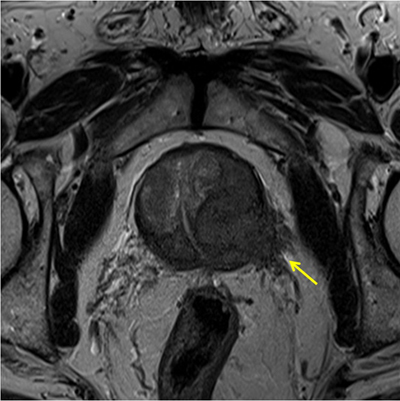

전립선암은 전립선에 암세포가 발생하는 질환입니다. 전립선의 일부 세포가 정상 세포의 성장을 조절하는 능력을 상실하고 통제할 수 없을 정도로 성장하여 악성 종양이 되는 질환입니다. 일반적으로 전립선암은 주로 전립선 상피 세포에서 발생하는 선암으로, 약 70~80%가 전립선 말초 부위에서 발생합니다.

뼈나 관절계의 통증이 항상 전립선암을 나타내는 것은 아니지만, 가장 먼저 살펴봐야 할 증상 중 하나입니다. 전립선암은 골반 림프절, 척추, 골반 뼈와 같은 전립선 주변 조직으로 전이되는 경우가 드물기 때문에 이러한 부위에 설명할 수 없는 통증이 있으면 의사와 상담하는 것이 중요합니다. 일부 남성은 허리, 엉덩이 또는 전립선 근처 부위에 통증을 느끼지만 단순한 신경통이나 관절통으로 치부하기도 합니다.

전립선암 초기증상 - 8. 골반통

골반 통증은 진행성 전립선암의 징후일 수 있습니다. 통증은 일반적으로 옆구리, 배, 골반 부위에서 느껴지지만 암이 진행됨에 따라 뼈에서도 통증이 느껴질 수 있습니다. 이러한 부위에 통증이 있고 요로 감염 증상이 나타나면 의사를 방문하여 정확한 진단을 받는 것이 좋습니다.